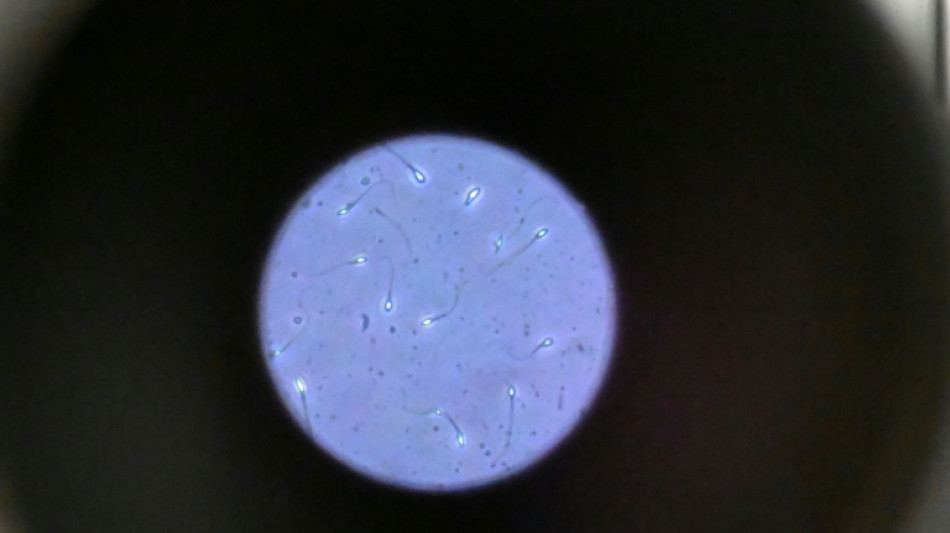

Dans l'espace, les spermatozoïdes ont du mal à trouver leur chemin / Photo: © AFP/Archives

Dans l'espace, les spermatozoïdes ont du mal à trouver leur chemin vers l'ovule en raison de la microgravité, qui perturbe aussi le développement des embryons, selon une étude publiée jeudi dans Communications Biology.

Les chercheurs ont testé successivement du sperme de souris et humain dans ce dispositif placé dans un appareil en constante rotation pour simuler la microgravité.

Les gamètes ont été environ 50 % moins performants pour naviguer à travers ce parcours que sous la gravité terrestre. Cela équivaut à une baisse de 30% du taux de fécondation réussie, selon les résultats de l'étude.